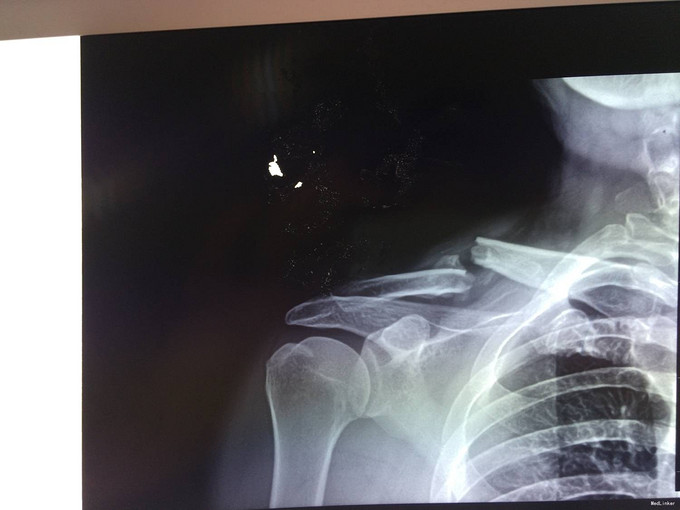

主诉:骑车摔伤后右肩部疼痛肿胀4小时 现病史:患者及家属自诉于2013年6月22日上午9点骑自行车摔倒致右肩部疼痛,肿胀,活动受限,当时无意识不清,到新民市当地医院,行X线片检查示:右锁骨骨折,未行治疗。现患者为求进一步治疗来我科,以“右锁骨骨折”为诊断收住入院。伤来患者无头痛及发热,无咳嗽咳痰,无腹痛及恶心呕吐,饮食睡眠可,大小便正常。

专科查体:右上肢吊臂带固定中,右肩部轻微肿胀,右锁骨处压痛(+),活动受限,骨擦感存在,右上肢无明显麻木,桡尺动脉清楚,各手指活动无受限。